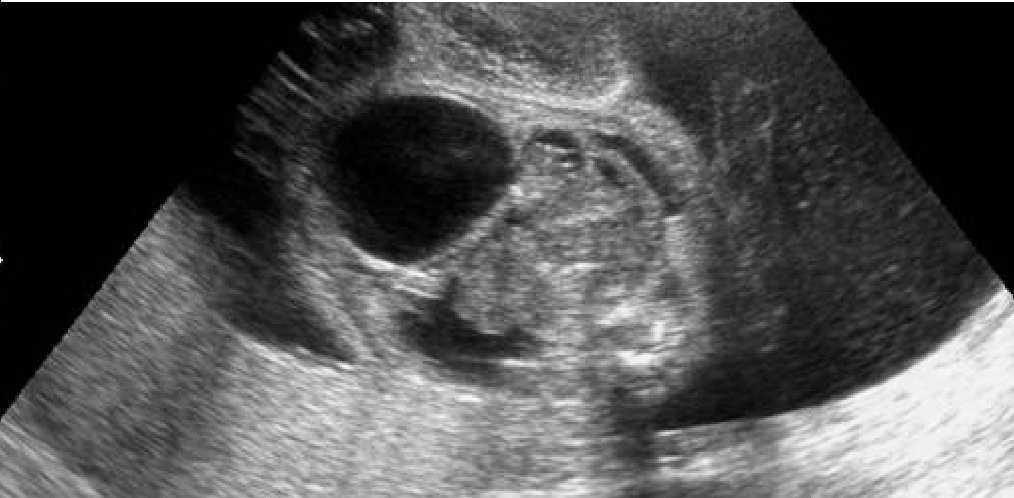

Gestante de 34 años de edad, sin antecedentes patológicos de interés, con antecedentes obstétricos de un aborto espontáneo y una cesárea anterior, realizada en el año 2003, en que dio a luz un recién nacido que falleció por depresión neonatal y síndrome de distrés respiratorio. Fue remitida en su tercera gestación a la unidad de Diagnóstico Prenatal del Hospital Universitario Materno Infantil de Canarias en la semana 21. El feto estaba en presentación cefálica, con movimientos activos espontáneos y una biometría acorde con la edad gestacional. La placenta era normoinserta y la cantidad de líquido amniótico era normal. Destacaba la presencia de una tumoración lumbosacra de 38 × 38 × 42 mm de diámetro, de contorno bien definido, contenido mixto con predominio sólido, localización lumbosacra, con componente intrapélvico que ocupaba la fosa ilíaca derecha fetal. No afectaba a la región genital, y los genitales externos masculinos eran normales. No había relación con el sistema urogenital ni con la columna (figs. 1 y 2). El estudio con Doppler color reveló una densidad vascular moderada y dependiente de los vasos paravertebrales, sin flujos turbulentos. El resto del estudio morfológico transcurrió dentro de la normalidad, sin evidencias de alteraciones en otras estructuras. Asimismo, se completó el estudio descartando la presencia de signos de sobrecarga cardíaca o de anemia fetal (índice de pulsatilidad de ductus venoso dentro de la normalidad, con un valor de 0,56; velocidad máxima de flujo en arteria cerebral media de 24 cm/s, no sugestivo de anemia fetal). Se concluyó la exploración con la orientación diagnóstica de teratoma sacrococcígeo tipo II, de componente mixto, moderadamente vascularizado, sin signos de insuficiencia cardíaca.

Figuras 1 y 2. Ecografía realizada en la semana 21, donde se aprecia una tumoración lumbosacra de 38 × 38 × 42 mm, de contenido mixto, contorno bien definido, con componente intrapélvico, que ocupa la fosa ilíaca derecha fetal.